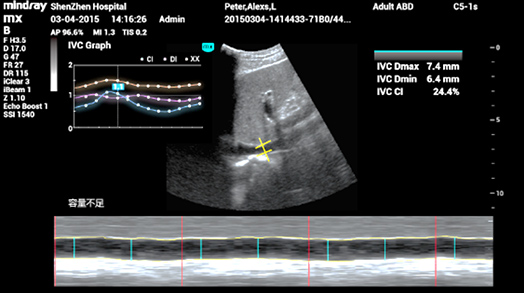

3Smart IVC

La medición automática de los parámetros de la VCI (vena cava inferior) ayuda a evaluar el estado del volumen y guía la terapia de fluidos. Gráfico de cambio de parámetros sobre CI o DI e IVCV para monitorear el cambio de pacientes en estado crítico.

3